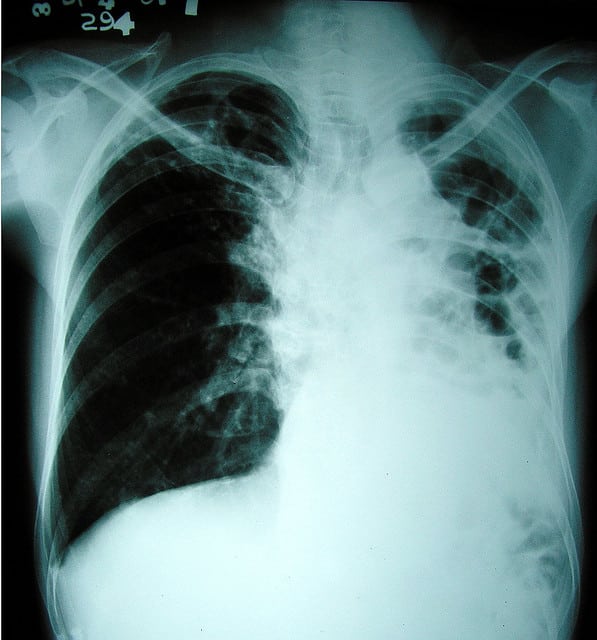

Plusieurs associations ont interpellé jeudi les gouvernements et plus spécialement le gouvernement français pour qu’ils continuent à financer la lutte contre la tuberculose qui tue 1,4 million de personnes chaque année dont 40% en Afrique.

“Face à cette épidémie qui tue plus de 4.000 personnes par jour, la France a choisi la stratégie de l’inaction”, écrivent plusieurs associations parmi lesquelles Aides, Solidarité Sida, Act Up Paris et Oxfam-France, dans un communiqué publié avant la journée mondiale de lutte contre la tuberculose qui sera célébrée dimanche.